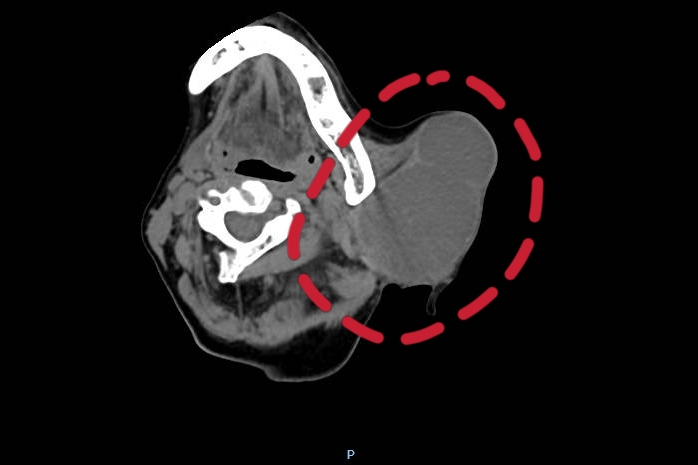

口腔科劉彥杰副主任醫師介紹,吳阿姨的腫瘤已經超過7CM,已經快要占據整個半邊臉,由于腫瘤過大,壓迫神經時間過長,神經已經受壓變得很細小,部分神經甚至與腫瘤相連,周圍部分組織也已經發生了粘連,此類疾病除了根除腫瘤以外,更應考慮如何在手術同時修復大面積缺損和保留面部神經功能,術中操作要非常注意,避免損傷到頸部大血管和生命中樞,一旦損傷,后果不堪設想。

經過多次討論,口腔科團隊制定了詳細的診治方案——左腮腺腫瘤切除術及顯微神經吻合術。劉彥杰副主任醫師帶領口腔科團隊歷經4小時,順利完成了手術,最終成功為患者切除了腫物并進行了神經吻合。